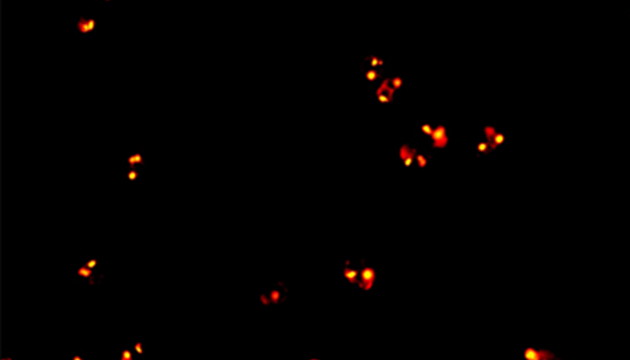

CTC檢測用于上皮腫瘤,如胃腸癌、皮膚癌等。檢測分四步:富集、CD45染白細胞、CK染CTC、DAPI染核。有DAPI、CK熒光且無CD45熒光,大核細胞為CTC;有DAPI、CD45熒光為白細胞。